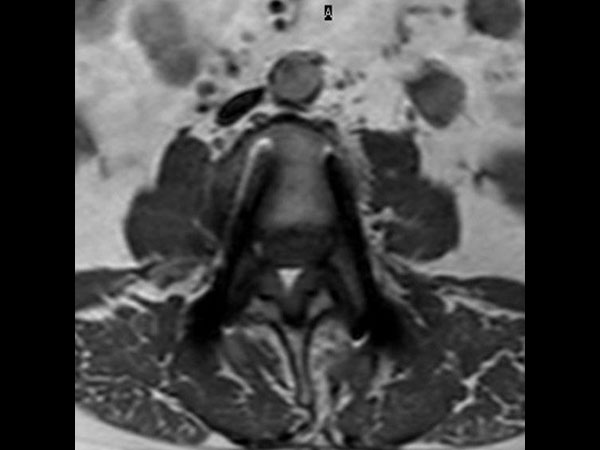

Lumbar Spine with metal implant, routine and fast

Utrecht Medical Center, The Netherlands

**Only for use with MR Safe or MR Conditional Implants by strictly following the Instructions for Use.